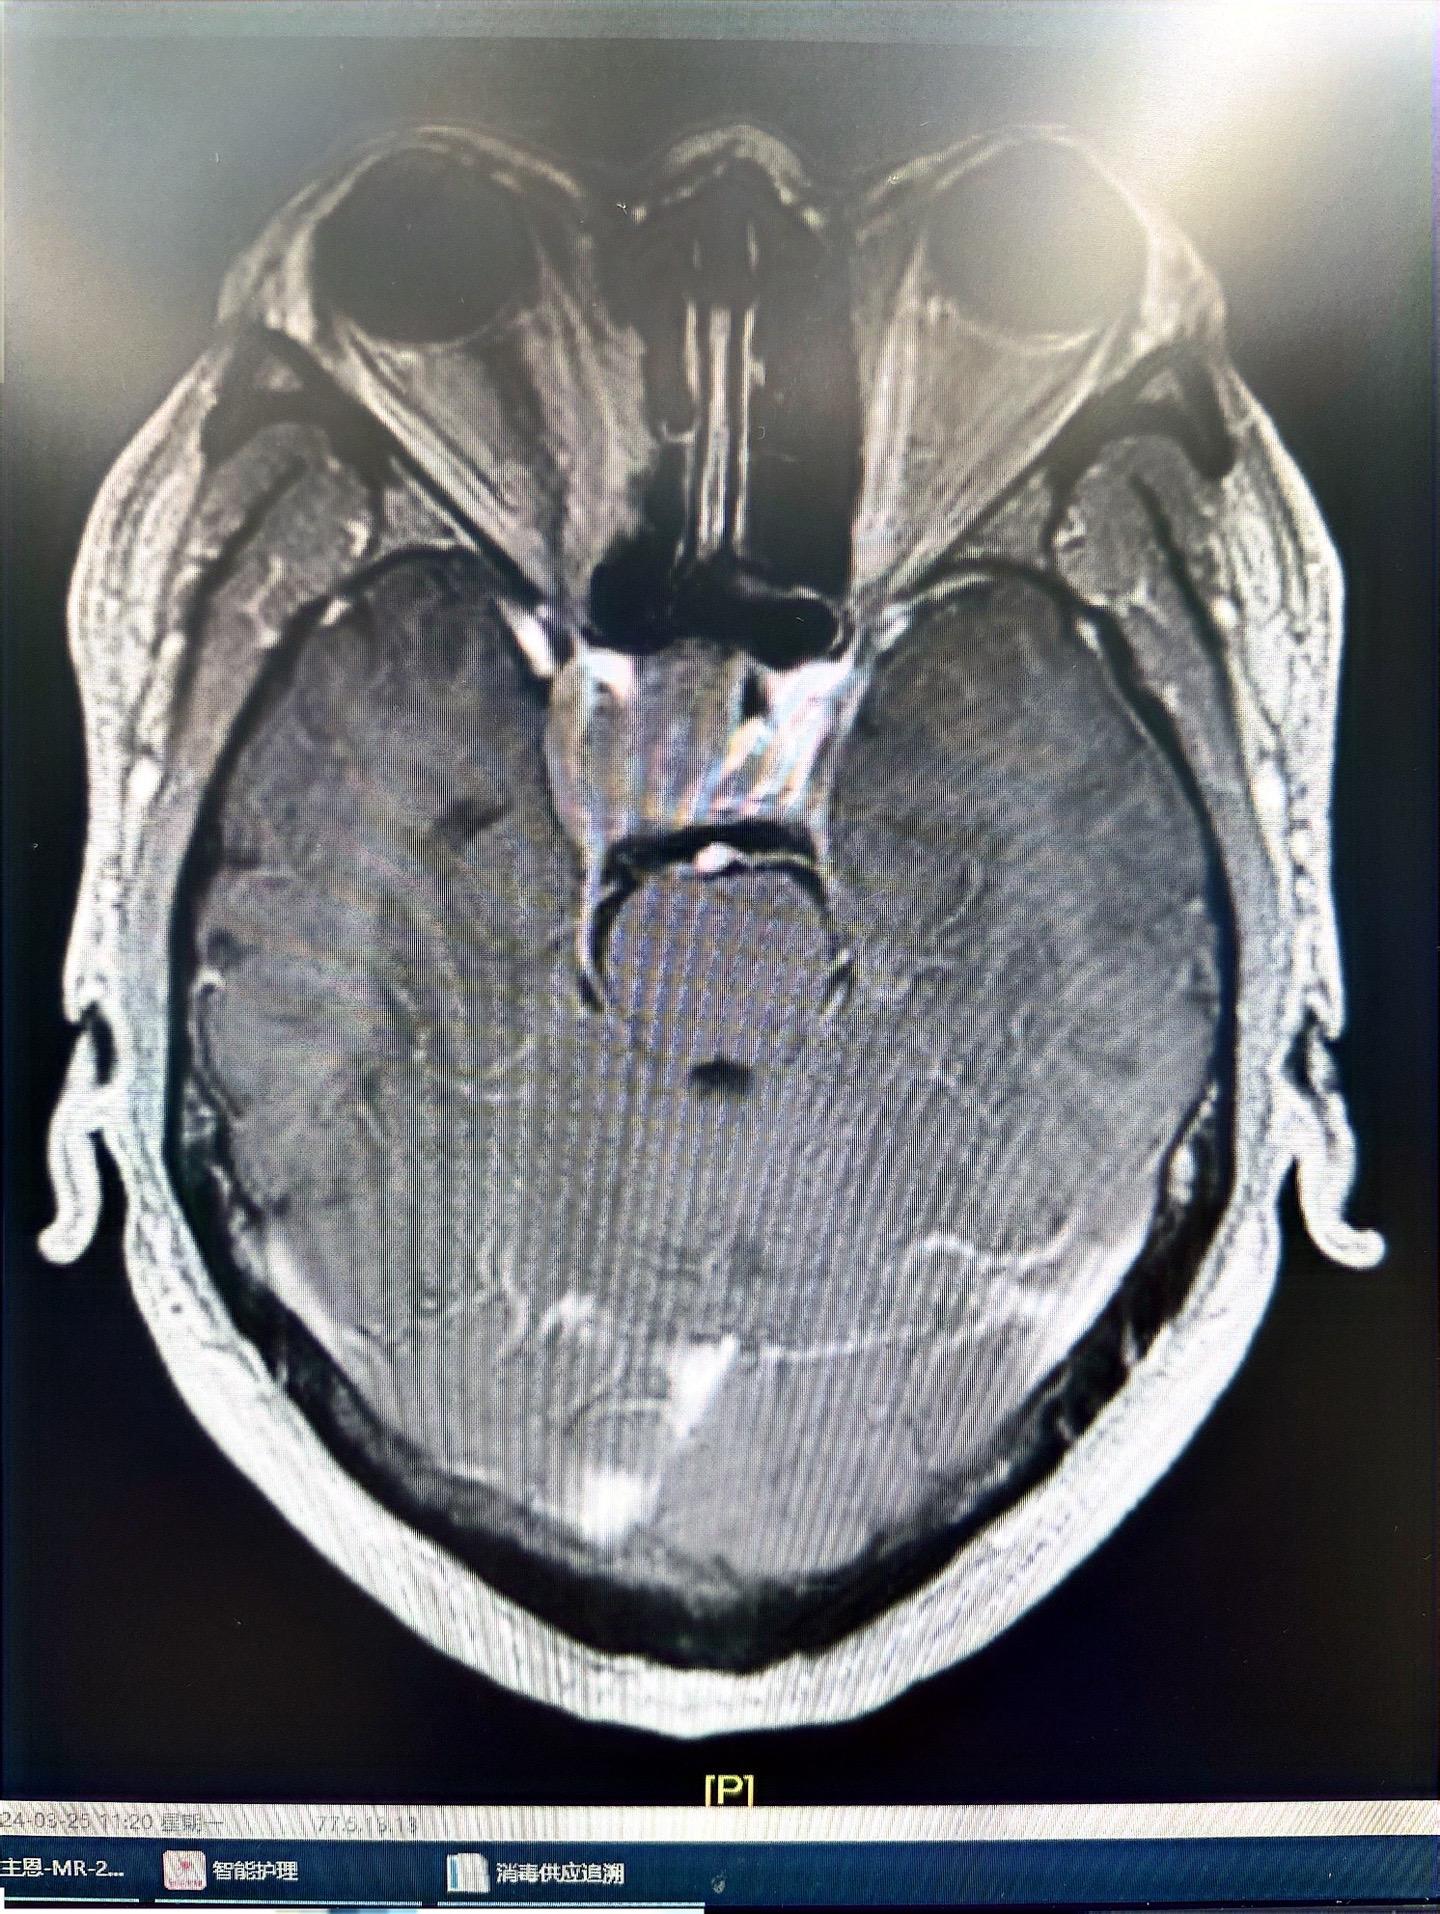

垂体瘤(生长激素型)分泌型垂体肿瘤难度还是较大,经鼻子手术,双镜联合,同时术中磁共振辅助,术后生长激素终于恢复正常!